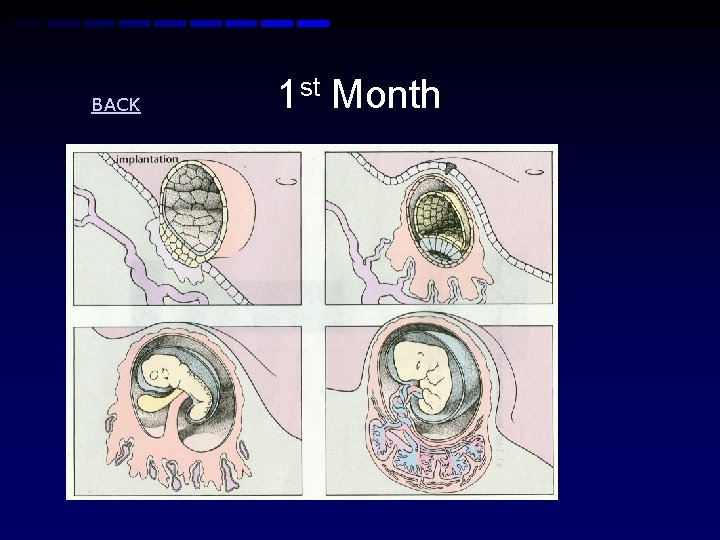

Week 3 • Beginning development of the brain, spinal cord, and heart • Nervous system first to develop • Beginning development of the gastrointestinal tract 1 st Month Diagram

BACK 1 st Month